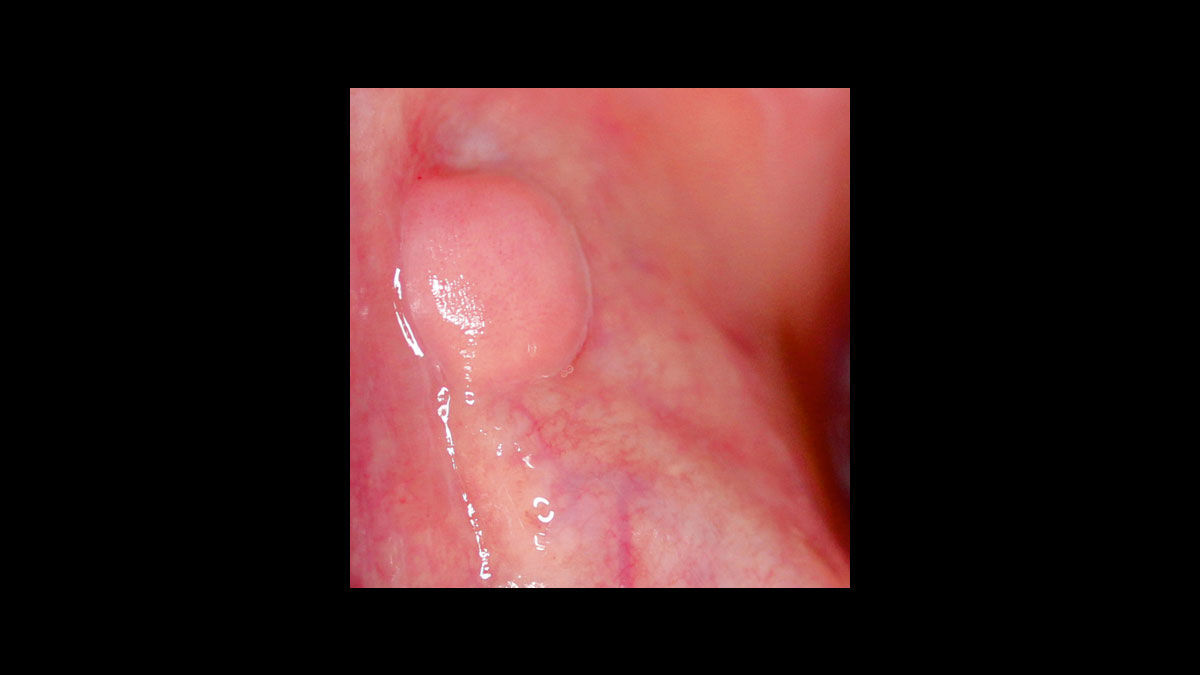

• Absceso

Fibroma

Frenectomía

Operculectomía